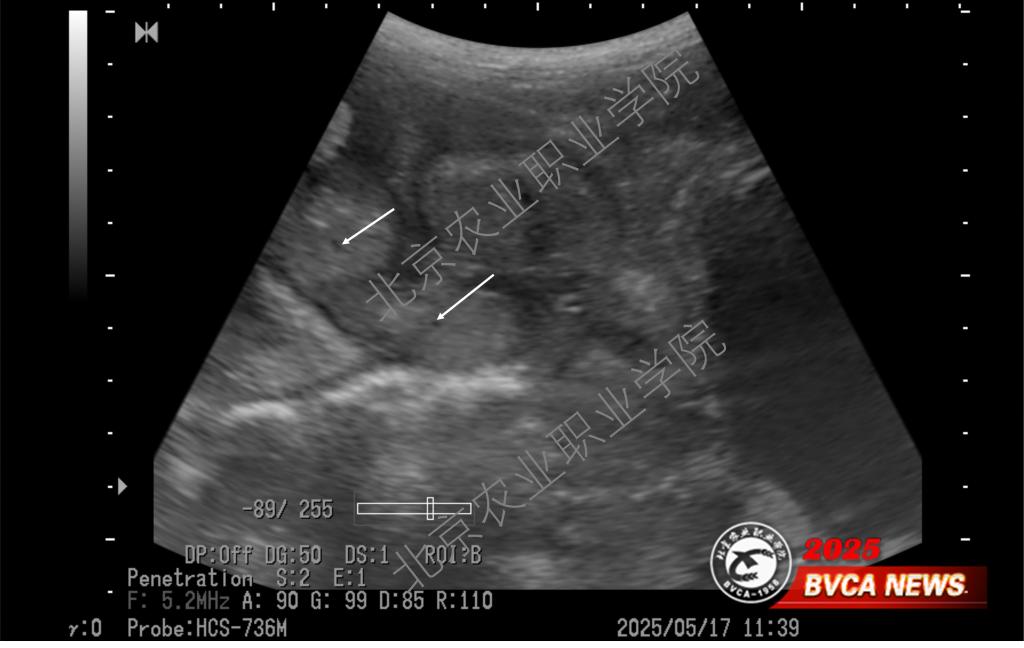

近日,受北京伟杰信生物科技有限公司邀请,动物科技学院兽医超声技术团队为该公司“母猪妊娠21天超声检查技术操作规范”项目提供了重要的技术支撑,并取得重大进展。团队首席专家姜晨副教授梳理了母猪不同体位超声扫查的方法,以便技术人员在不改变母猪体位的情况下做出准确诊断,最大程度上降低怀孕母猪不必要的应激。

近年来,我院姜晨副教授领衔的兽医超声技术团队积极推广超声影像技术在多种动物临床中的应用,并取得一系列技术成果。团队持续探索母猪孕早期超声检查的边界,目前最早可在排卵后第9天确认是否怀孕(可见直径约1mm的卵囊液)。此超声检查技术已达到国际前沿水平,为打开母猪孕初相关的科学研究之门提供了一把金钥匙。